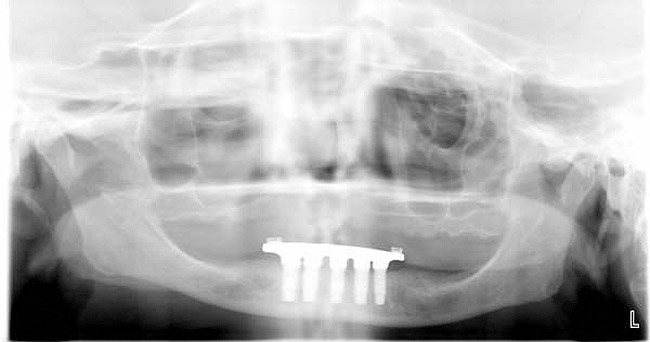

Figure 3   A crown height space < 15 mm necessitates a PFM material selection.

Figure 3

For large-segment/full-arch fixed prostheses, the critical distance is 15 mm. If the distance from the implant platform to the occlusal table is less than 15 mm, then the prosthetic material indicated is porcelain-fused-to-metal (PFM) (Figure 3). If the distance is greater than 15 mm, then a hybrid prosthesis should be used (Figure 4).

The 15-mm measurement is important because of the physical properties of the restorative materials. Acrylic requires bulk for strength. If there is less than 15 mm of distance from the implant platform to the occlusal table, there will not be sufficient space to achieve the bulk of acrylic necessary to provide strength for the prosthesis. The unfortunate result will be continual repair of fractures for the life of the prosthesis.

Likewise, PFM restorations have difficulties when too much space is available. At dimensions greater than 15 mm from the implant platform to the occlusal table, the control of surface porosity across the metal substructure becomes difficult because of variations in cooling and heating rates across the metal,10 which in turn makes it difficult to bake porcelain to the metal substructure. The result is the high possibility of future unwanted complications of porcelain fracture.11